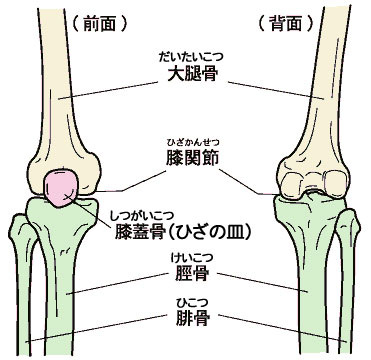

下半身 骨 イラスト. 本記事では、「4下半身の塗り方」より、凹凸が出やすく形に気をつける必要のある「膝」の描き方、塗り方についての解説をご紹介します。 >この連載の他の記事はこちら >前回の記事はこちら 美少女イラストのリアルな肌の塗り方 膝の塗り方を知ろう. 人体の骨の名称と数を解剖のイラストを用いて詳しく解説 人間にはどんな骨があるのでしょうか? 今回は人の骨の名称を解剖図を見ながら学んでいきましょう。 これを読めば人体にどんな骨があるのかかなり理解できるようになりますので、最後まで. 今回は、運動前に行うことでケガの予防だけでなく パフォーマンスにも大きく影響します ダイナミックストレッチの効果や 代表的なメニューの紹介をしていきます。 基本的なメニューになりますがしっかりと意識をして行いましょう。 また各競技のレベルによってメニューを変えてみて.

膝 の構造を理解して自然な表現を心がけよう 美少女イラストのリアルな肌の塗り方 第9回 Pictures

イラスト図解 ひざ関節 足 下半身の構造 骨 筋肉 靭帯 腱の名称や働き

イラスト図解 ひざ関節 足 下半身の構造 骨 筋肉 靭帯 腱の名称や働き

イラスト図解 ひざ関節 足 下半身の構造 骨 筋肉 靭帯 腱の名称や働き

画像 ひざ関節の解剖図 前後 看護ノート 解剖学 筋肉解剖学